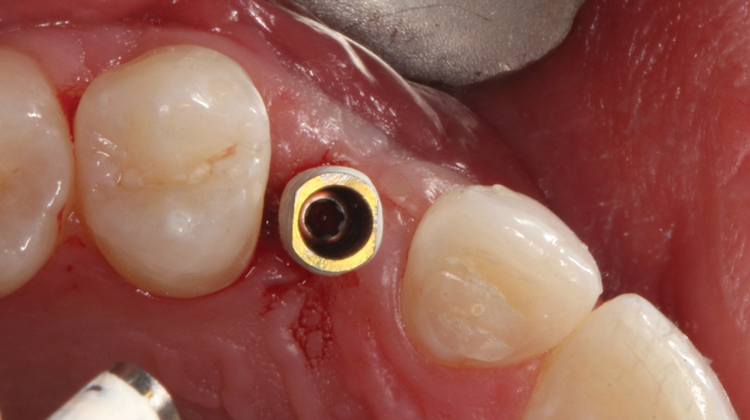

(17.) Close-up view of the titanium temporary abutment in place after being coated with composite opaquing resin.

Figure 17

(38.) The opaqued titanium provisional abutment was gently tightened onto the implant.

Figure 38